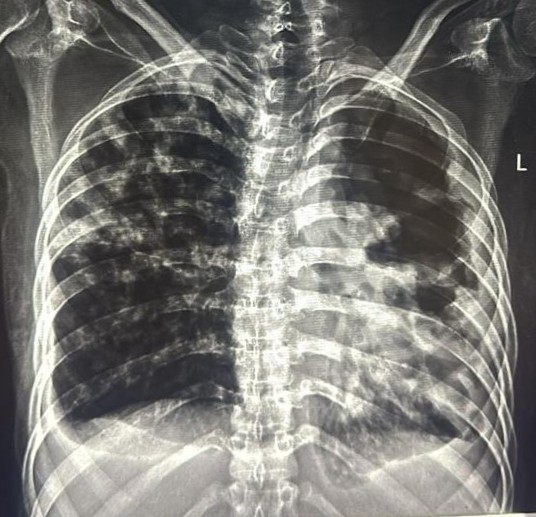

| 207 | IGGMC, Nagpur, Nagpur | P2 | 29-4265 | SHUBHAM MARATHE | Consent taken on Paper | 27 Yrs. |

Provisional Diag : LEFT SIDED CLINICALLY DIAGNOSED PLEURAL EFFUSION

Final Diag : LEFT SIDED CLINICALLY DIAGNOSED TUBERCULAR EMPYMA ON ATT FROM 9.11.2024 |

TB Case (Confirmed) | LEFT SIDED CP ANGLE BLUNTING | Abnormality visible on x-ray |